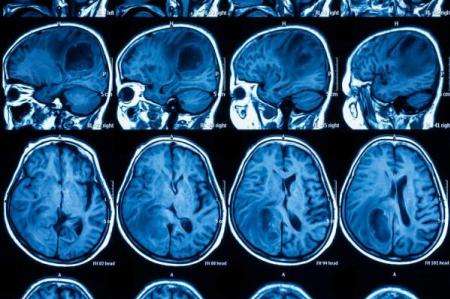

محققان دانشگاه کارولینای شمالی در مطالعه ای روی موش ها متوجه شدند که این سلول های بنیادی بقایای سلول های تومور مغزی را پیدا کرده و از بین می برند.

گلیوبلاستما (یک نوع سرطان مغز)، تومورهای تهاجمی و سریع الرشد هستند که آستروسیت ها یعنی سلول هایی را تشکیل می دهند که بافت حمایت کننده مغز را می سازند.

محققان در این مطالعه که در مجله Nature Communications منتشر شد، سلول های پوستی به نام فیبروبلاست ها را دوباره برنامه ریزی کردند تا به سلول های بنیادی خنثی تبدیل شوند و یک پروتیین از بین برنده تومور تولید کنند.

محققان سپس این سلول ها را به موش تزریق کردند و با کمک یک ماتریکس (ماده بین سلولی)فیزیکی آنها را در محل نگاه داشتند تا به اندازه کافی زمان برای کشف سلول های سرطانی داشته باشند.